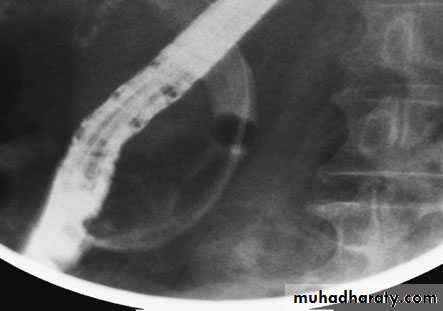

68Endoscopic retrograde cholangiopancreatography: thepatient presented with jaundice 4 days after laparoscopic cholecystectomy.The bile duct contained multiple stones